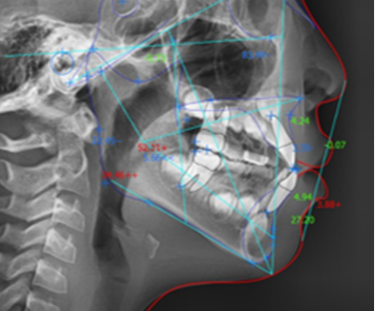

치열 상태와 구강 구조를

디지털 장비를 통해 정밀히

검사하여 문제점을 진단합니다.

3D CT, 구강 스캐너 등 다양한 디지털 진단 장비를 통해

얼굴 라인과 치아 본연의 기능을 고려하여 개인 맞춤 계획을

세우기 때문에 만족도 높은 교정 결과를 기대할 수 있습니다.